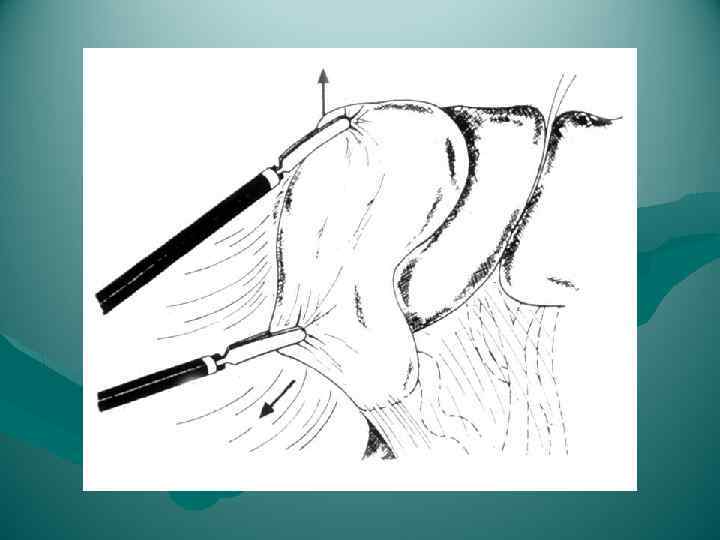

ЭТАПЫ ОПЕРАЦИИ ТИПИЧНОЙ ХОЛЕЦИСТЭКТОМИИ 1. Лапаротомия 2. Обнажение желчного пузыря 3. Выделение, перевязка и пересечение ductus cysticus и a. cystica 4. Выделение желчного пузыря из его ложа и удаление 5. Перитонизация ложа пузыря 6. Зашивание раны брюшной стенки ЭТАПЫ ОПЕРАЦИИ ЛАПАРОСКОПИЧЕСКОЙ ХОЛЕЦИСТЭКТОМИИ 1. Оперативный доступ 2. Выделение желчного пузыря из сращений с окружающими тканями 3. Выделение, клипирование и пересечение пузырного протока и пузырной артерии 4. Отделение желчного пузыря от печени 5. Извлечение желчного пузыря из брюшной полости

ЭТАПЫ ОПЕРАЦИИ ТИПИЧНОЙ ХОЛЕЦИСТЭКТОМИИ 1. Лапаротомия 2. Обнажение желчного пузыря 3. Выделение, перевязка и пересечение ductus cysticus и a. cystica 4. Выделение желчного пузыря из его ложа и удаление 5. Перитонизация ложа пузыря 6. Зашивание раны брюшной стенки ЭТАПЫ ОПЕРАЦИИ ЛАПАРОСКОПИЧЕСКОЙ ХОЛЕЦИСТЭКТОМИИ 1. Оперативный доступ 2. Выделение желчного пузыря из сращений с окружающими тканями 3. Выделение, клипирование и пересечение пузырного протока и пузырной артерии 4. Отделение желчного пузыря от печени 5. Извлечение желчного пузыря из брюшной полости

ЭТАПЫ ЛАПАРОСКОПИЧЕСКОЙ ХОЛЕЦИСТЭКТОМИИ 1. Оперативный доступ 2. Выделение желчного пузыря из сращений с окружающими тканями 3. Выделение, клипирование и пересечение пузырного протока и пузырной артерии 4. Отделение желчного пузыря от печени 5. Извлечение желчного пузыря из брюшной полости

ЭТАПЫ ЛАПАРОСКОПИЧЕСКОЙ ХОЛЕЦИСТЭКТОМИИ 1. Оперативный доступ 2. Выделение желчного пузыря из сращений с окружающими тканями 3. Выделение, клипирование и пересечение пузырного протока и пузырной артерии 4. Отделение желчного пузыря от печени 5. Извлечение желчного пузыря из брюшной полости